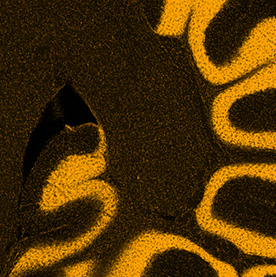

Many processes within the body are changed by the presence of cancer. These images show the response of microglia, immune defense cells in the brain, to cancer cells. When microglia encounter glioblastoma multiforme, one of the most aggressive brain cancers, they shift from a relaxed, elongated shape to a rounded, ready-for-combat conformation.

These images echo the work of Anna Atkins, a British botanist and photographer who used a contact printing technique called cyanotyping to capture the form of plants and algae. Emily Chen’s work similarly seeks to explore biological function, in this case the immune response to brain cancer, by capturing and comparing biological forms.

This triptych shows three views of the folds of a mouse cerebellum, a part of the brain that helps control fine motion. In this form of artwork, the three panels create a story by highlighting a central figure with supporting imagery to either side. This triptych highlights the use of different stains for different features: yellow for the DNA inside brain cells, blue for support cells surrounding neurons. By layering multiple stains, researchers can understand how those elements interact in living tissues.